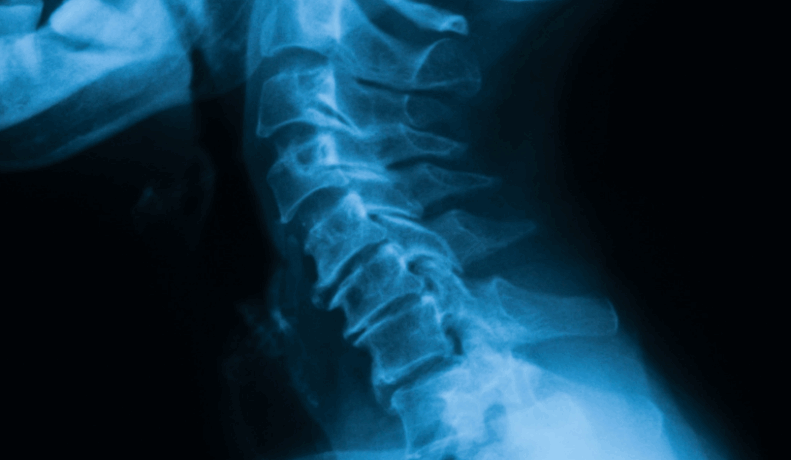

Lordoza cervikale është harku natyral i shtyllës kurrizore në qafë. Në raste të caktuara, ky hark mund të humbasë formën e tij normale (drejtim ose shtrembërim), duke shkaktuar dhimbje dhe kufizim të lëvizjes. Ky problem lidhet shpesh me qëndrime të gabuara, punë të gjata para kompjuterit, trauma ose degjenerim të…